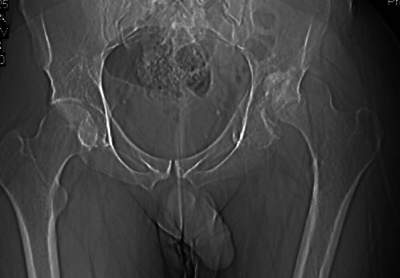

важаемые коллеги,пациент 23 лет (вес 75 кг), обратился к нам по поводу боли в тазобедренном суставе при ходьбе, нестабильность в нем при нагрузке. Ходит с тростью. 8 мес. назад попал в ДТП (никаких медицинских документов у него нет). Стоит ли открываться и вправлять вывих или сразу делать бесцементное тотальное эндопротезирование? С уважением, А. В. Вакуленко Клиника эндопротезирования суставов, г. ДонецкDear All, male patient 23 y.o., body weight 75 kg. Had RTA 8 months ago (medical records unavailable). Now has pain on motion in his left hip. On weight-bearing hip is unstable (patient use cane while walking). Keeping in mind his age, is it worth to perform open reduction? Or just do uncemented THR? Any comments are very welcome.

After 8 months, the hip will not easily come down into the acetabulum. It also appears to me that there is an impression fracture of the head of femur.

у нас есть несколько пациентов с похожей ситуацией после

открытых вправлений в приблизительно такие же сроки, часть из них

устраивает качество жизни, несмотря на явления аваскулярного

некроза и коксартроза (человека 4). Конечно все закончится

эндопротезированием рано или поздно, но пока ходят.

Здравствуйте. Позвольте поучаствовать в обсуждении. Поскольку пациент в течение 8 месяцев не получил адекватного лечения (видимо и по своей вине тоже), а также учитывая удовлетворительное состояние головки бедра(по данным КТ), есть смысл выполнить открытое вправление головки бедра с возможной фиксацией фрагмента заднего края пластиной. Далее начать восстановление функции сустава, дозированную нагрузку. Возможно молодой возраст пациента поможет ему отдалить время эндопротезирования. Желаю успехов.